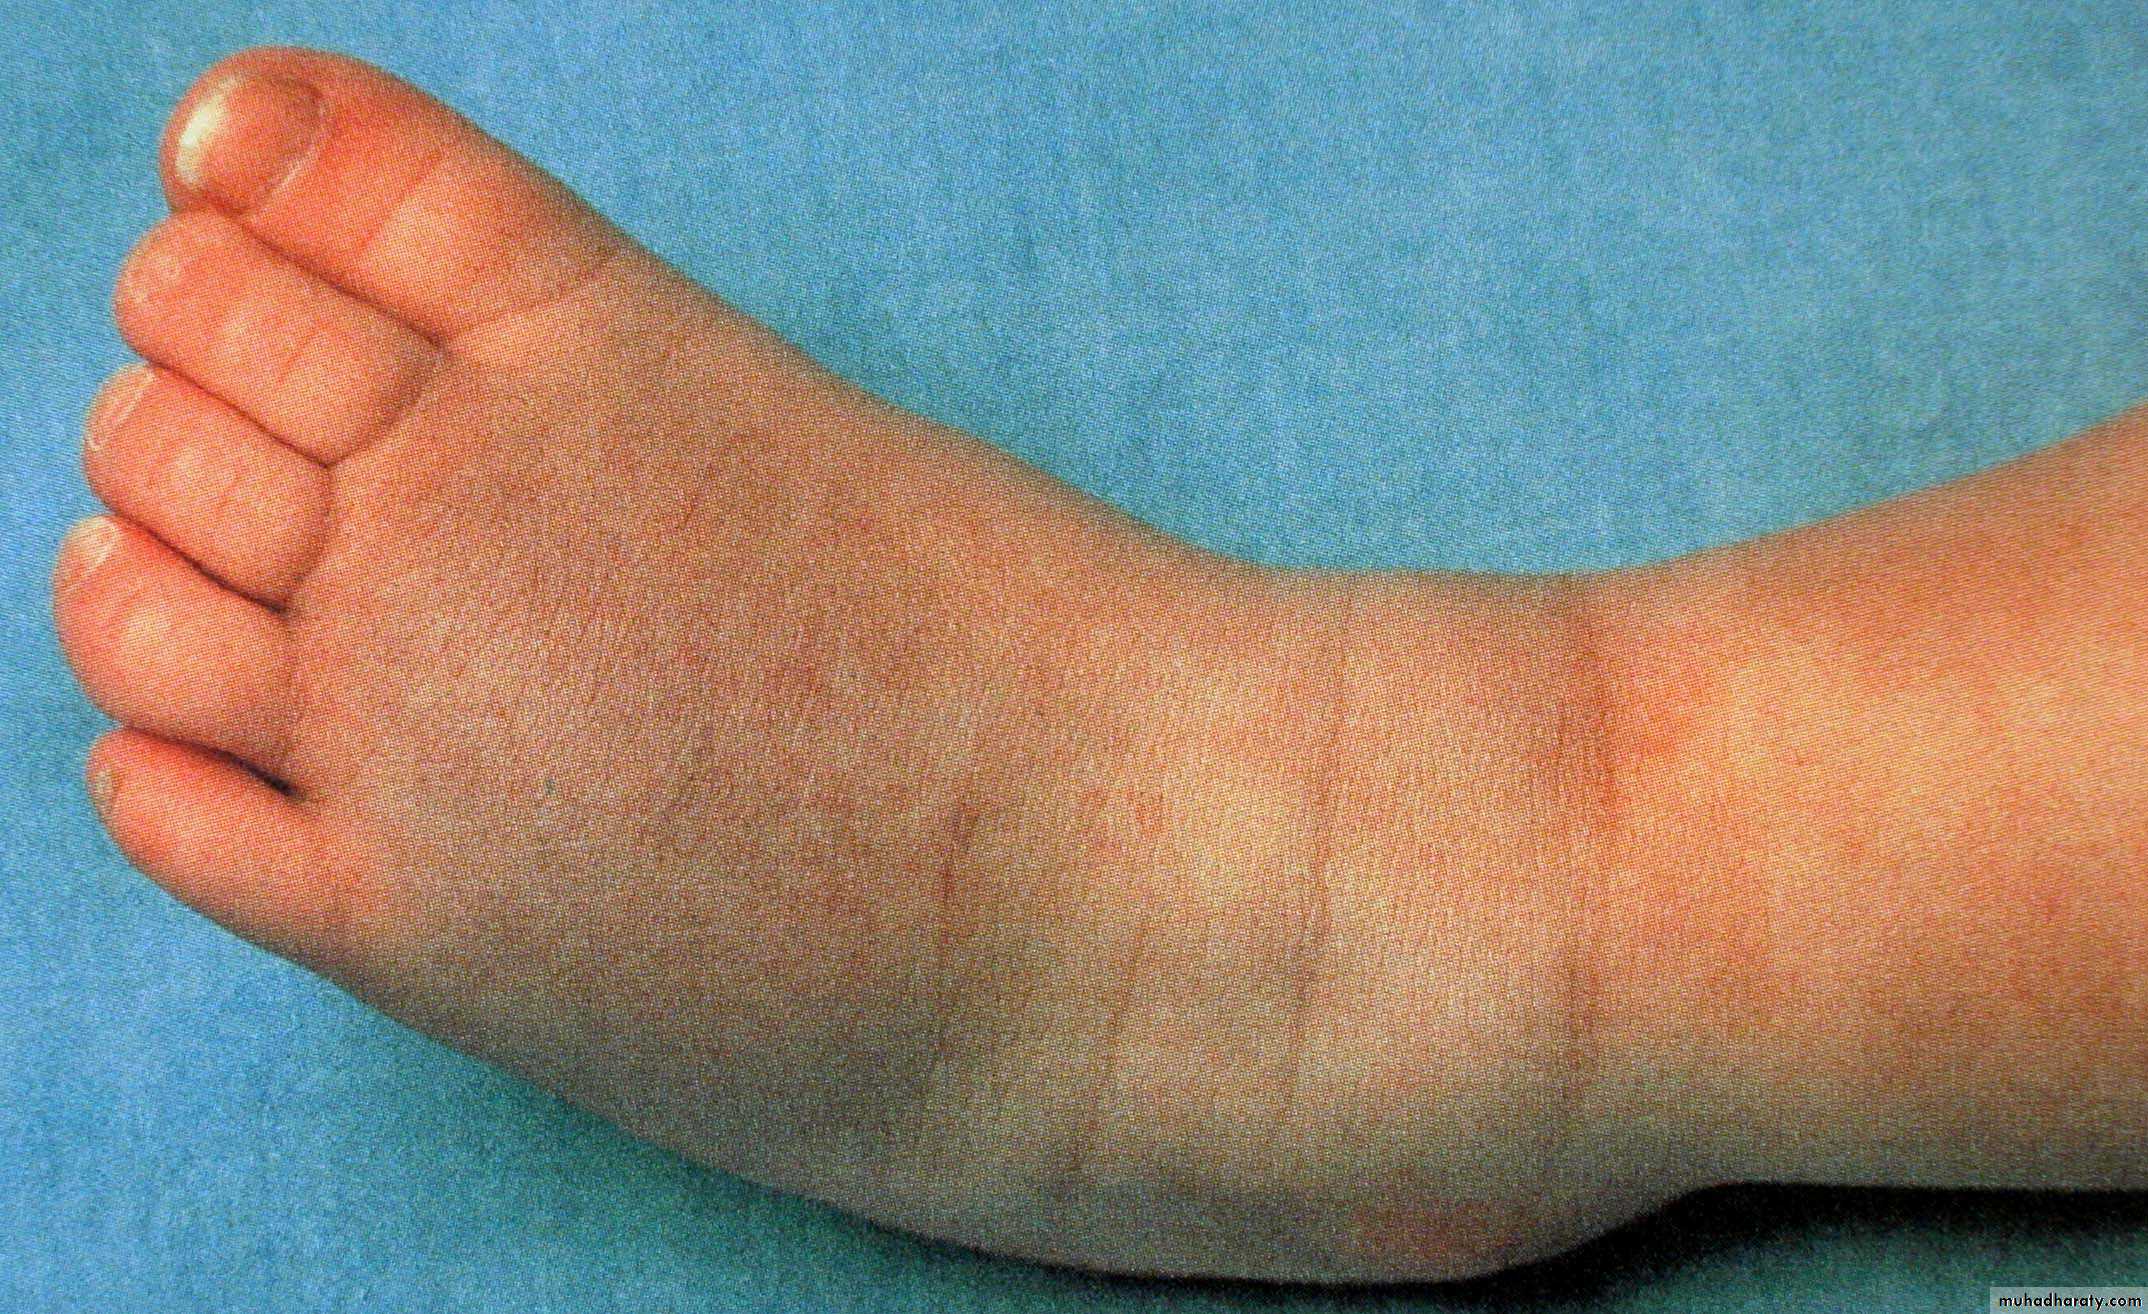

Ankle bleed

CLINICAL PRESENTATION

Bleeding has a prediliction for joints, particularly weight bearing.

HaemarthrosisAlso bleed intramuscularly

HAEMOPHILIA - HAEMARTHROSIS

CHRONIC JOINT BLEEDING

Which joint bleeds are most common?

Most common ankles, knees, and elbows – weight bearing jointsBleeds in other joints can also happen, including the toes, shoulders, and hips.

What happens in a joint bleed?

joint feels tingly and warm.Swelling, painful and difficult to move.

Long-term effects of Joint bleeds?

Repeated bleeding causes synovium (lining) to swell

The synovium stops producing the slippery, oily fluid that helps the joint move.

Damages the cartilage- joint stiff, painful and unstable.With time, most of the cartilage breaks down and some bone wears away. The whole process is called haemophilic arthropathy.

What Happens in a Muscle bleed?

During a bleed, the muscle feels STIFF and PAINFUL.The bleed causes SWELLING that is WARM and PAINFUL to touch.

In some deeper muscles, the swelling may press on nerves or arteries, causing TINGLING and NUMBNESSmuscle SPASM.